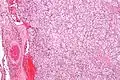

Micrograph of a carotid body tumor

The paragangliomas appear grossly as sharply circumscribed polypoid masses and they have a firm to rubbery consistency. They are highly vascular tumors and may have a deep red color.

On microscopic inspection, the tumor cells are readily recognized. Individual tumor cells are polygonal to oval and are arranged in distinctive cell balls, called Zellballen.[8] These cell balls are separated by fibrovascular stroma and surrounded by sustentacular cells.